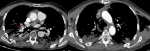

The patient tested positive for SARS-CoV-2 reverses transcriptase-polymerase chain reaction test (RT-PCR) performed on nasopharyngeal swabs. According to these clinical and biological findings, a computed tomography pulmonary angiography (CTPA) was performed, which showed acute bilateral pulmonary embolism (Figure 1). Chest computed tomography (CT) scan also revealed subpleural ground-glass opacities associated with multiple areas of consolidation suggestive of COVID-19 pneumonia as well as the presence of bilateral pneumothorax, pneumomediastinum, and extensive bilateral subcutaneous emphysema (Figure 2 A, B, C, D). The patient was transferred to the intensive unit care and received treatment with azithromycin 250mg once a day, ceftriaxone 2g once a day, ciprofloxacin 400mg twice a day, hydrocortisone, tocilizumab unique dose, therapeutic anticoagulation with low molecular weight heparin (LMWH), and supplemental oxygen on high-flow nasal cannula (HFNC). The pneumothorax required bilateral drainage with bubbling, and the pneumomediastinum was managed conservatively. However, the patient further deteriorated with acute respiratory failure, which required intubation with mechanical ventilation in volume-controlled mode controlled (the fraction of inspired oxygen (FIO2) at 100%, and positive end-expiratory pressure (PEEP) of 8cm H20 was applied. A chest X-ray (Figure 3 A) showed the pneumothorax persistence on the right side. He benefited from a re-drainage by a drain of Joly 24 with X-ray control (Figure 3 B). Unfortunately, he deceased from respiratory failure 10 days after admission.

Figure 1: computed tomography pulmonary angiography in axial lung window showing acute bilateral pulmonary embolism (red arrows)

Figure 2: chest CT scan in coronal (A, B) axial (C, D) and lung parenchymal windows showing subpleural ground-glass opacities associated with multiple areas of consolidation as well as the presence of bilateral pneumothorax, (yellow arrows) pneumomediastinum, (red arrows); extensive bilateral subcutaneous emphysema (white arrows)